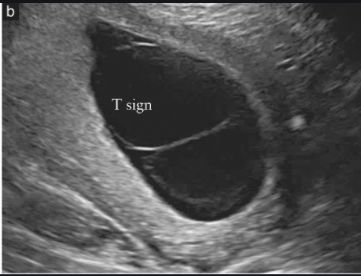

"T sign" is the sonographic image seen in a _____chorionic twin pregnancy.